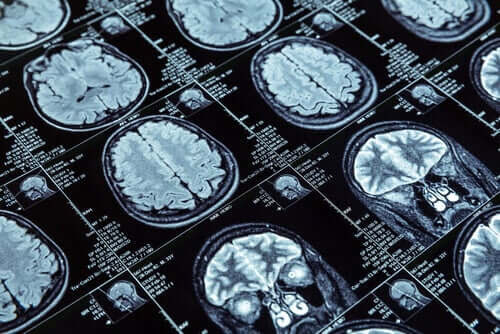

För att genomföra forskningen genomförde de kärnmagnetisk resonans på över 600 personer som alla var 45 år gamla när bildtestet utfördes. Dessa 600 personer var en del av en större grupp på över 1 000 personer. Forskare från Nya Zeeland har studerat dessa människor sedan barndomen.

De mätte tjockleken på hjärnbarken och mängden grå substans genom resonanser som de utförde på forskningsdeltagarna. Denna information möjliggjorde en jämförelse mellan de som visade upp antisocialt beteende och de som inte gjorde det.

Forskarna lärde sig viktiga saker från den första gruppen. MR-skanningar från dessa människor visade att hjärnbarken krympt jämfört med de andra. Dessutom hade de en något mindre mängd grå substans.

Till exempel hade tonåringar med antisociala problem förändringar i hjärnans frontala och temporala lober. Vad som är allvarligare är att våldsamma fångar har mindre grå substans.

Forskare hade även tittat närmare på det emotionella området i hjärnan för att hitta en koppling. Förutsatt att antisociala problem beror på brist på empati var det logiskt att leta efter förändringar där. Resultaten visade att antisociala tonåringar har en mindre hypofys, och amygdala, vilket är området för empati.